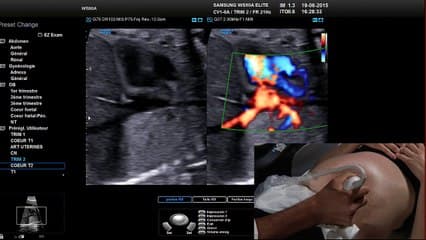

Edwin QUARELLO présente avec tout son sens pdégogique connu les fondamentaux du dépistage de l'examen cardiaque fœtal en live. A regarder sans modération !